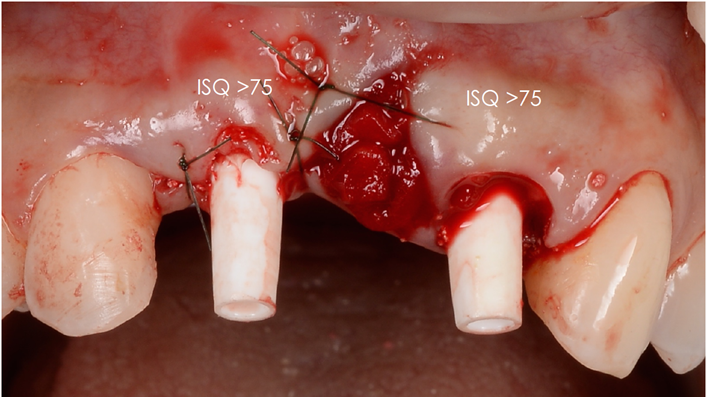

“AnyRidge is perfect for the anterior esthetic zone due to its strong initial stability & fast osseointegration.

Plus, KnifeThread® ensures space maintenance when using the PET/Socket Shield/Root Membrane Technique, showing excellent bone growth.”